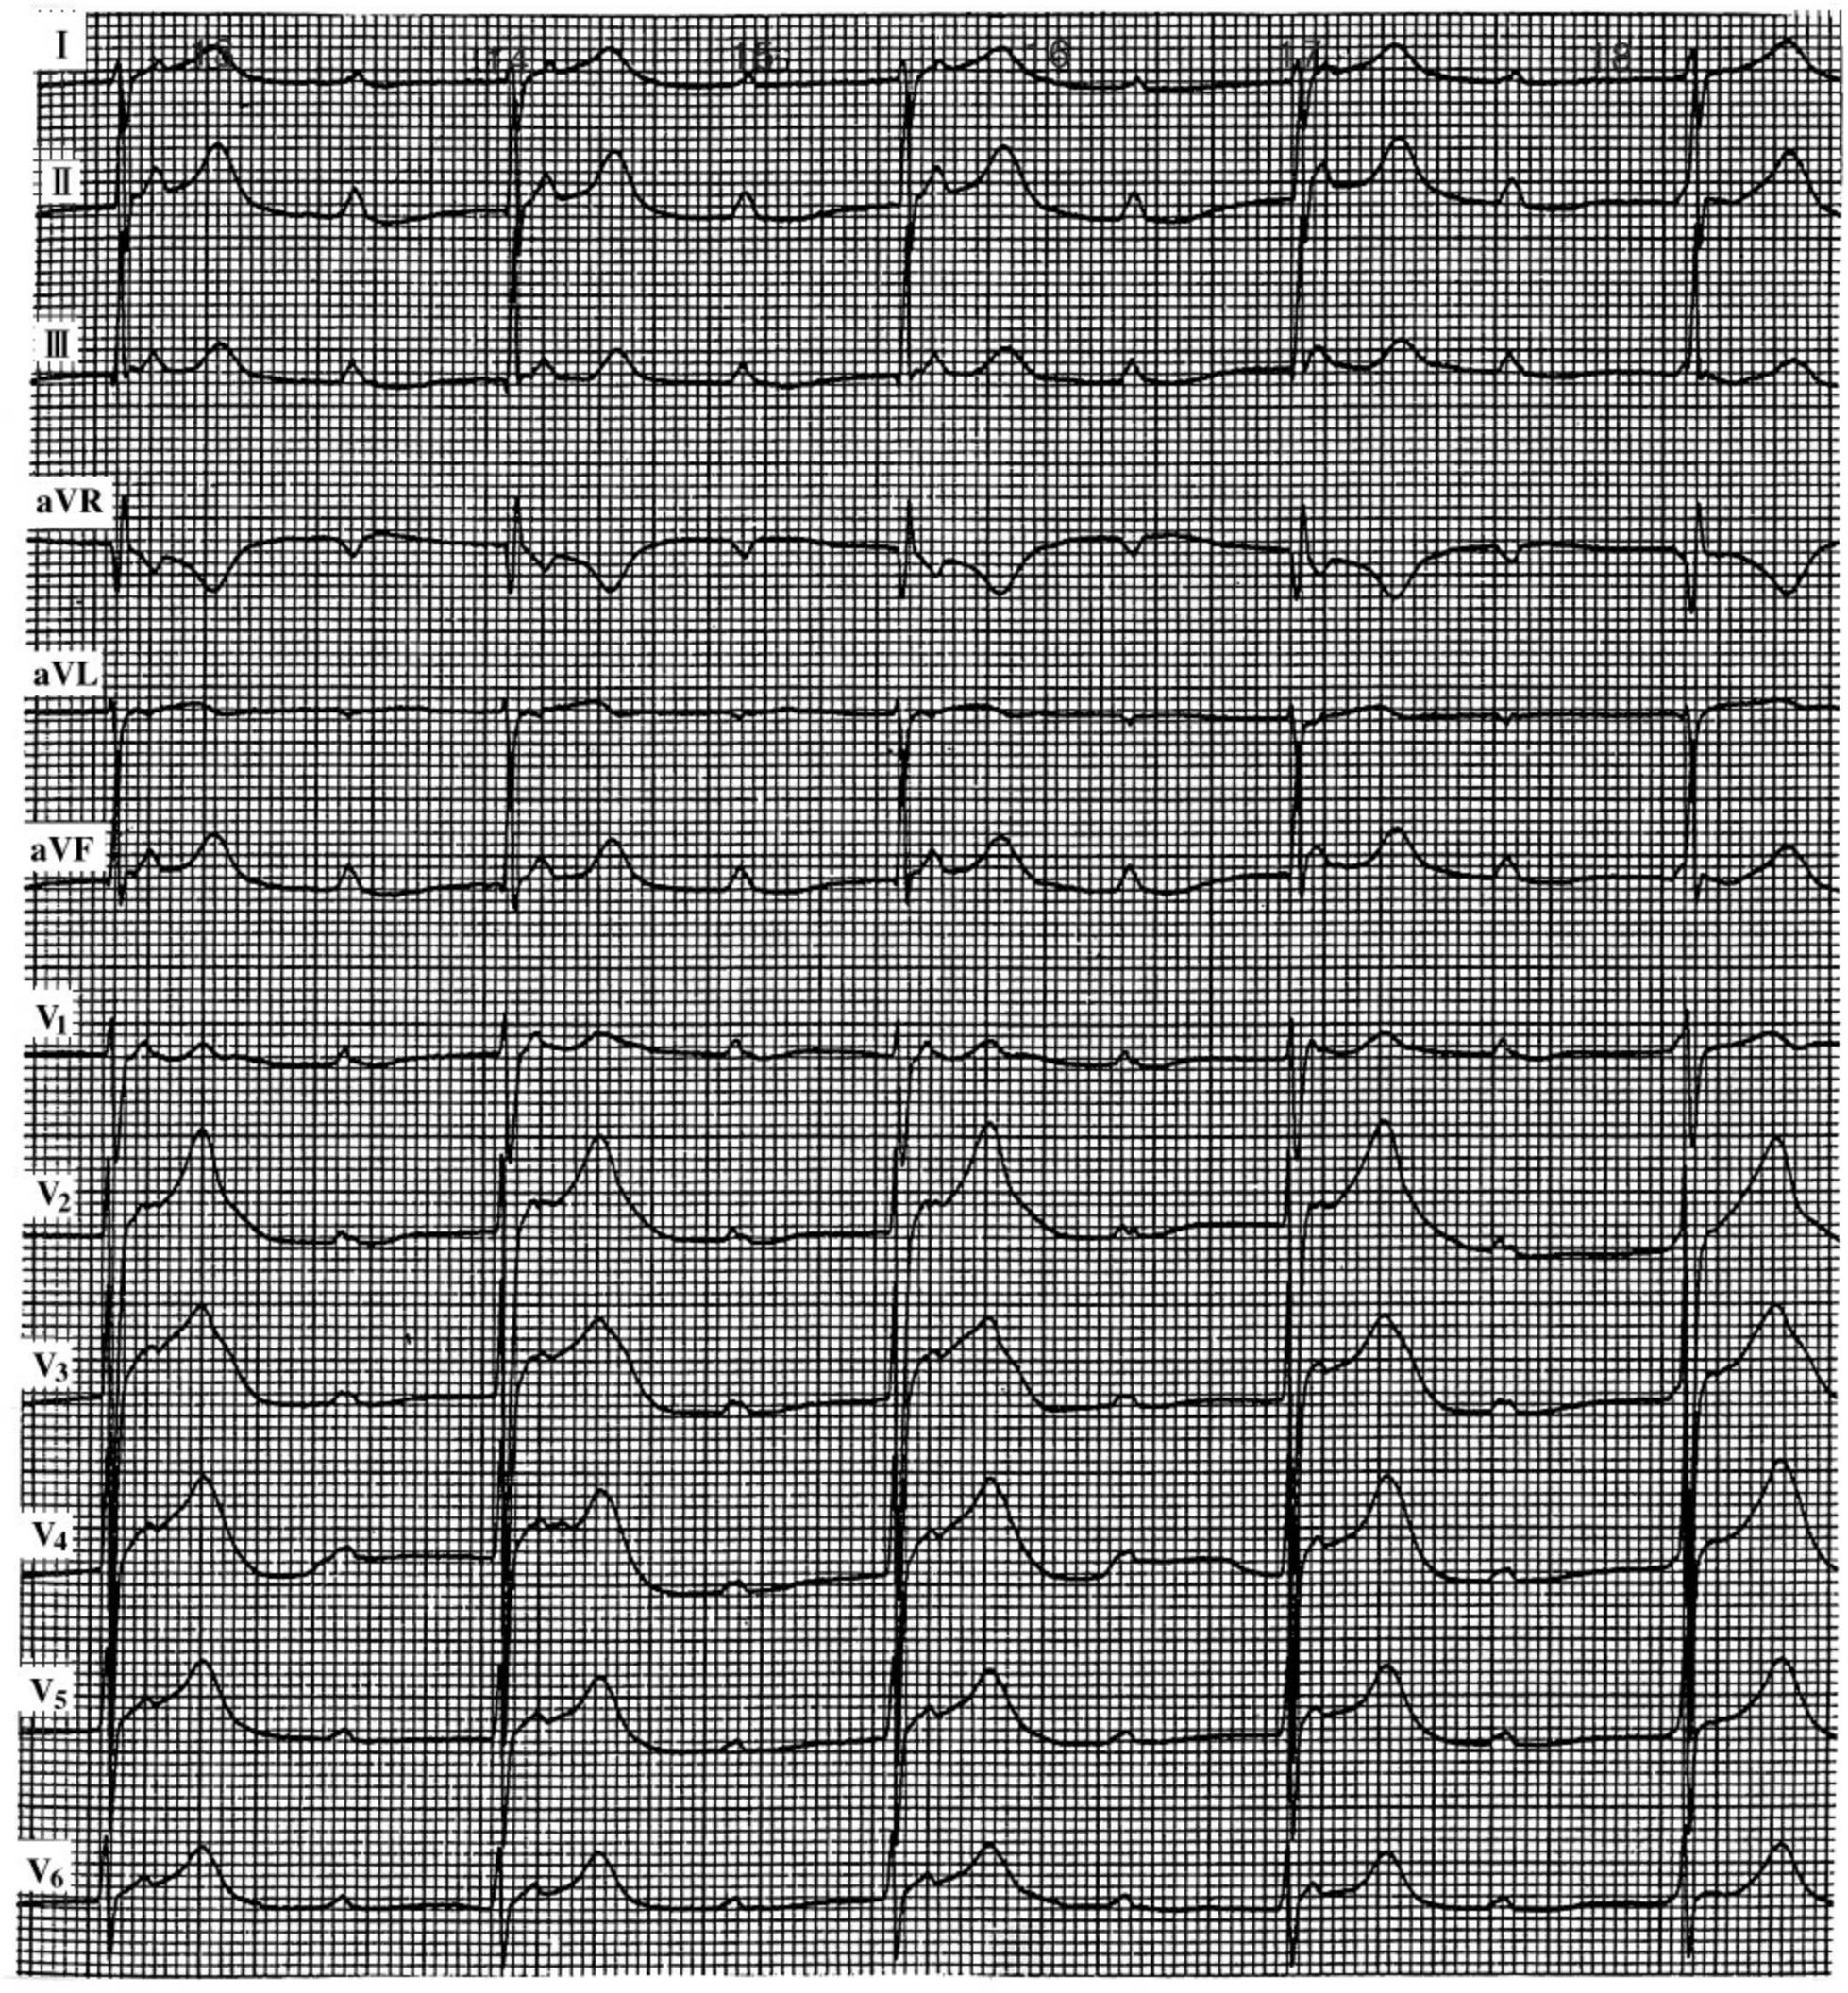

img331

图21-1 预激综合征合并房颤

(四)预激综合征合并房颤 预激综合征(WPW)合并房颤时,心室率常大于180次/min,这是由于心房激动通过不应期极短的附加旁路所致。极度频速的室率,使到达心室的激动易进入心室肌易激期,而诱发室颤。如果两个连续R-R间期<0.20ms时,则预示有发生室颤的危险;缺血性心脏病,心肌炎患者R-R>0.20ms,也可发生室颤。心电图表现为(图21-1)快速、不规则的QRS波群,通常呈完全性预激波;如f波间歇通过正常的房室旁路前向传导,偶尔表现为正常的QRS波群。有时冲动可同时通过房室旁路和正常房室通道其同激动心室,形成室性融合波。预激综合征易误诊为室性心动过速,其鉴别要点见下表。